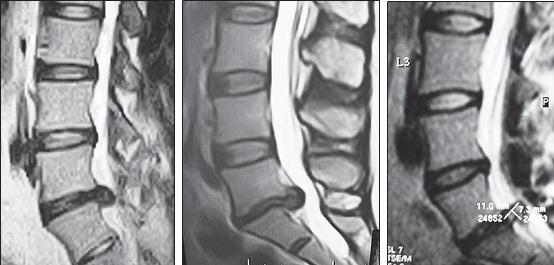

МРТ № 1

На магнитно-резонансной томографии (МРТ) № 1 — шейный отдел позвоночника, в относительно нормальном состоянии.

Шейный отдел позвоночника должен иметь нормально выраженный физиологический лордоз, не должно быть гиполордоза или гиперлордоза, а так же кифотических деформаций.

Ширина спинного мозга: сагиттально > 6–7 мм

1. Сагиттальный размер позвоночного канала на уровне:

СI 21 мм

СII 20 мм

СIII 17 мм

CIV-CVII = 14 мм

2. Высота межпозвонковых пространств:

СII < СIII < СIV < СV < СVII  СVII

3. Ширина спинномозгового канала: поперечный диаметр на уровне ножек: > 20–21 мм

МРТ № 3

На МРТ № 3 — поясничный отдел позвоночника. (На данном «контрольном» снимке наблюдаются остаточные явления дегенеративно-дистрофического процесса в сегменте LV-SI после устранения методом вертеброревитологии секвестрированной грыжи межпозвонкового диска.)

В поясничном отделе форма позвоночного канала, создаваемая телом и дужками позвонка, вариабельна, но чаще она пятиугольная. В норме позвоночный канал в пояснично-крестцовом отделе сужен в переднезаднем диаметре на уровне LIII и LIV позвонков. Его диаметр каудально увеличивается, и поперечное сечение канала приобретает форму, близкую к треугольной, на уровне LV-SI. У женщин канал имеет тенденцию к расширению в нижней части крестцовой области. Сагиттальный диаметр значительно уменьшается от LI к LIII почти неизменен от LIII к LIV и увеличивается от LIV к LV. В норме переднезадний диаметр позвоночного канала в среднем равен 21 мм (15–25 мм).

Существует простая и удобная формула определения ширины позвоночного канала:

нормальный сагиттальный размер не менее 15 мм;

11–15 мм — относительный стеноз;

менее 10 мм — абсолютный стеноз. Уменьшение этого соотношения свидетельствует о сужении канала.

Высота поясничных межпозвонковых дисков 8–12 мм, нарастает от LI до LIV-LV, обычно уменьшается на уровне LV-SI